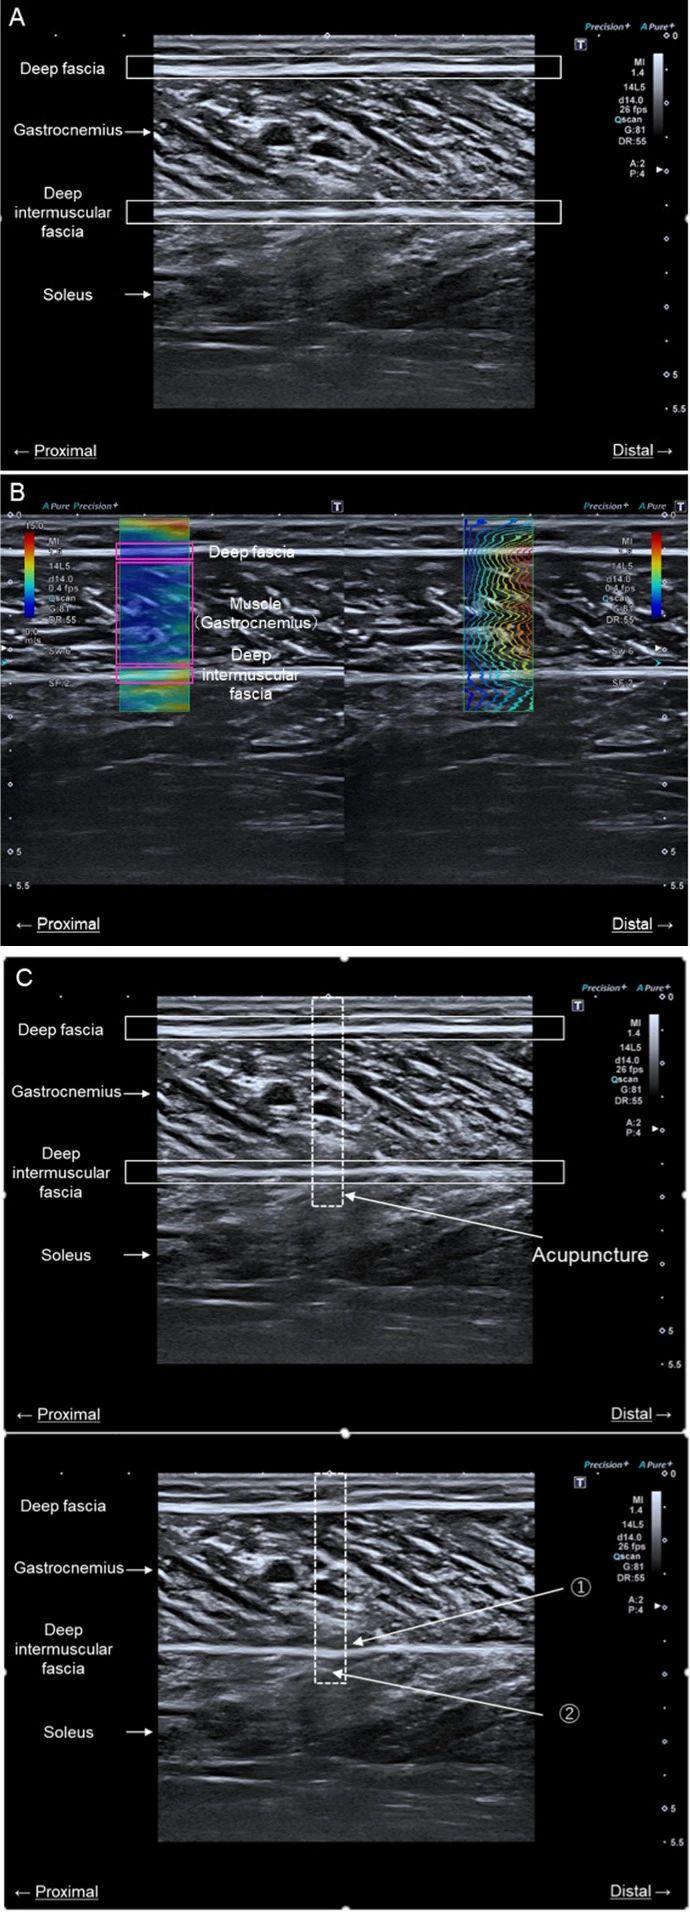

(A) 圖的這一部分顯示了一個尺寸為 6.5 cm × 1.0 cm 的標(biāo)記,該標(biāo)記與超聲探頭對齊。探頭位于小腿長度的 近端 30% 位置,這個位置信息是從 外側(cè)膝關(guān)節(jié)縫 到 外部囊 的距離。

(B) 這一部分展示了在進(jìn)行測量和應(yīng)用 低頻電針灸 時 下肢的位置。

(A) 圖中顯示的是腓腸肌內(nèi)側(cè)頭的超聲圖像。

(B) 圖顯示的是沿長軸測量肌肉和筋膜的剪切波速度的超聲圖像。

(C) 圖顯示了針灸針插入深度的確認(rèn)。使用超聲成像設(shè)備確定了以下兩個要點(diǎn):在進(jìn)行針灸時,DIF(深層肌間筋膜)是彎曲的;針灸點(diǎn)在DIF下方可見。虛線方框表示針灸針插入的區(qū)域。